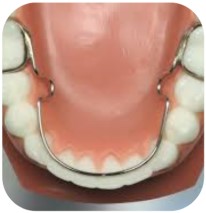

LİNGUAL ARK(lower lingual holding arch (LLHA)): LIngual ark (LLHA) yer koruyan bir apareydir. Alt birinci azı dişlerinize alt dişlerinizin iç tarafı boyunca uzanan bir tel ile bağlanan iki metal banttan oluşur. Bu cihazın amacı alt azı dişlerinizin hareket etmesini önlemektir.